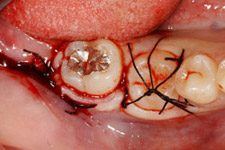

左:移植直後のエックス線写真。

右:移植後1ヶ月。

根管治療直後。歯根が完成している歯を移植歯として用いた場合、歯の神経はつながらないので、このように神経の治療が必要になります。